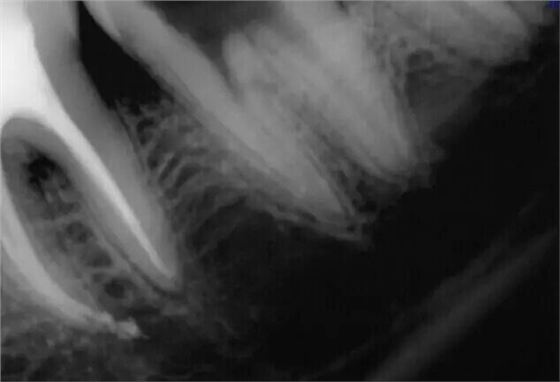

然后根充